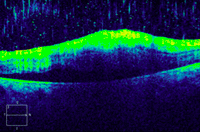

Figura 2. OCT de un ojo sano (Cirrus HD-OCT).